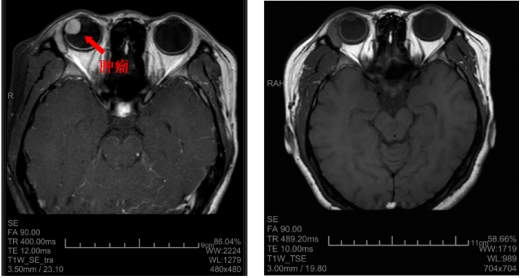

术前和术后的核磁影像学检查结果比较

孙大卫在裂隙灯显微镜下发现晓琳的右眼内有一肿瘤,散瞳后肉眼可见瘤体。进一步检查发现,肿瘤位于患者右眼颞侧12点至6点钟位,纵径接近180度,从晶状体蔓延到眼底赤道部,横径超过15mm(而正常人的眼球直径约23mm),肿瘤在眼内脉络膜生长,瘤体向眼球内突出,高度约12mm。综合测量评估后专家认为肿瘤占据眼内体积的一半以上,且肿瘤生长速度较快,已经造成患者视物的遮挡,并逐渐出现肿瘤相关的眼内并发症,渗出性视网膜脱离,继发性白内障等,病情仍有进一步恶化的可能,建议手术治疗。